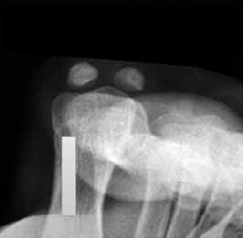

A seguir, observe a imagem de uma radiografia.

Assinale a alternativa que corretamente descreve o que está identificado na radiografia.